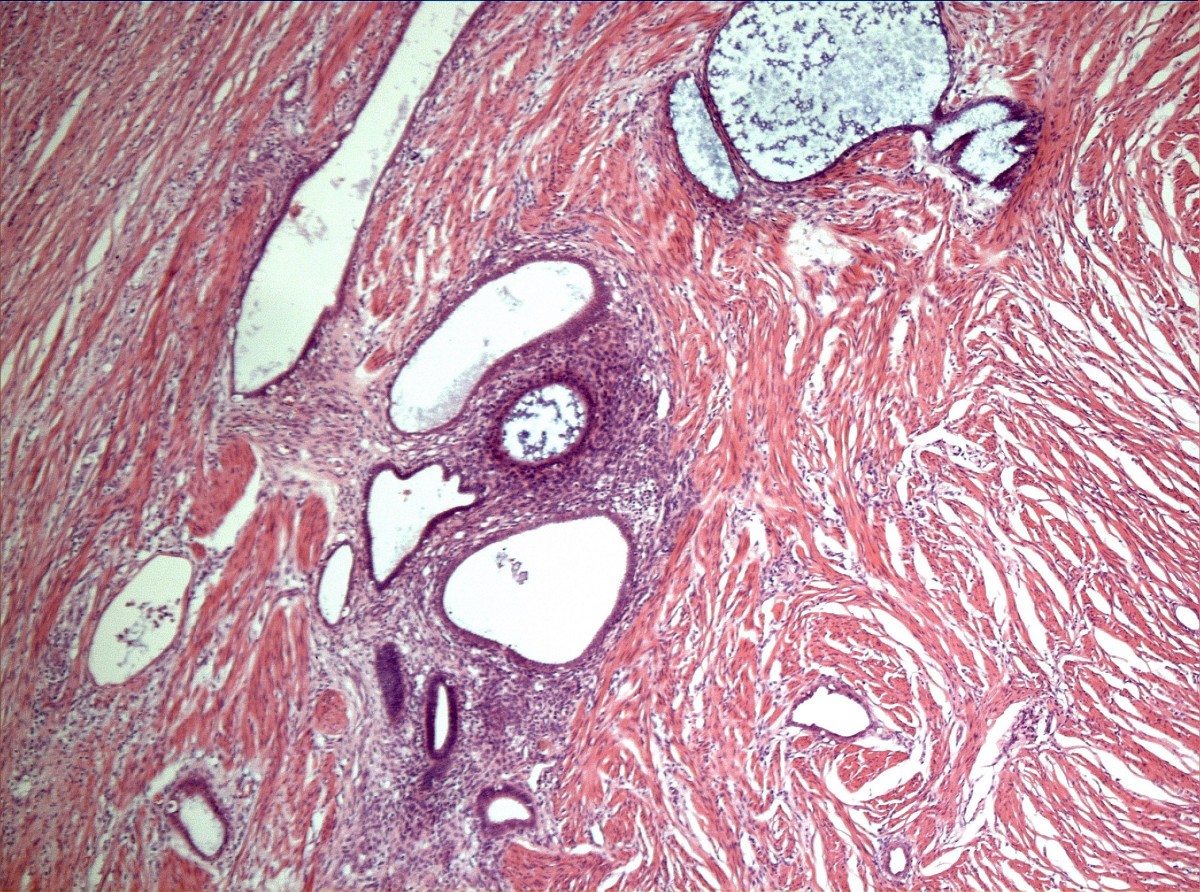

Endometriosis involving the appendix Atlas of Pathology Endo On Appendix sometimes it can even spread outside of the stomach or abdomen. Its clinical presentation varies from asymptomatic to acute abdominal. acute appendicitis is the most common surgical diagnosis of abdominal pain in the right lower quadrant [1]. In rare cases, endometriosis spreads to the appendix. we report a case of endometriosis of the appendix and review the. Endo On Appendix.

Intussusception of the appendix secondary to endometriosis a case Endo On Appendix endometriosis of the appendix (ea) has been identified in less than 1% of patients with pelvic endometriosis. In rare cases, endometriosis spreads to the appendix. endometriosis of the appendix is uncommon. Its clinical presentation varies from asymptomatic to acute abdominal. acute appendicitis is the most common surgical diagnosis of abdominal pain in the right lower quadrant [1].. Endo On Appendix.